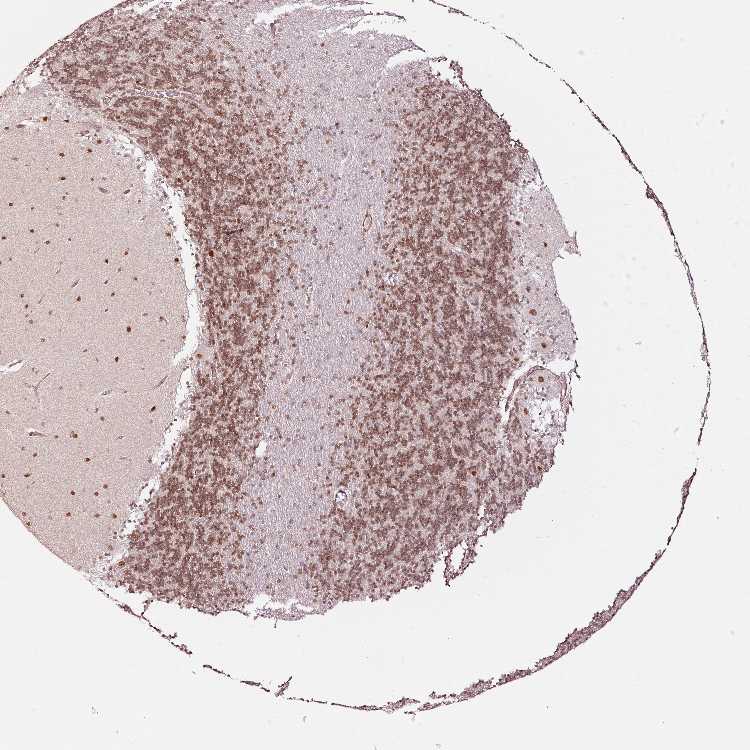

CEREBELLUM - Antibody stainingi

Antibody staining in the annotated cell types in the current human tissue is reported as not detected, low, medium, or high, based on conventional immunohistochemistry profiling in selected tissues. This score is based on the combination of the staining intensity and fraction of stained cells.

Each image is clickable and will lead to virtual microscopy that enables deeper exploration of all samples and also displays staining intensity scores, fraction scores and subcellular localization as well as patient and tissue information for each sample.

Antibody HPA047089Antibody HPA053624

Purkinje cells LowMedium

Cells in granular layer MediumMedium

Cells in molecular layer MediumHigh